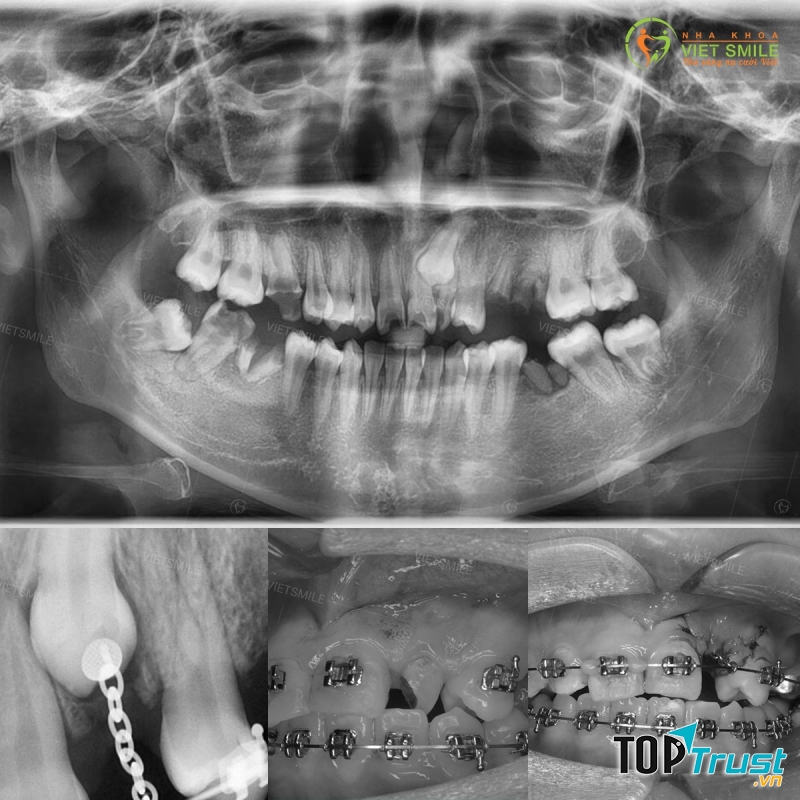

Nha Khoa VIET SMILE

Nha Khoa VIET SMILE là một trong những trung nha khoa uy tín tại Thanh Xuân, Hà Nội. Tuy mới được thành lập năm 2016 và chuyên sâu về các nghiệp vụ khó như thẩm mỹ răng, nắn chỉnh răng, cấy ghép Implant, chỉnh vẩu, vổ, răng mọc thưa. lệch lạc, niềng răng… Nhưng bằng uy tín, trách nhiệm và lương tâm nghề nghiệp mà Nha Khoa VIET SMILE đã nhanh chóng nhận được sự tin tưởng và những phản hồi tích cực từ phía khách hàng.

Nha khoa VIET SMILE được đầu tư các trang thiết bị chuyên dụng hiện đại. Được nhập khẩu từ các nước có nền nha khoa phát triển như Đức, Mỹ, Nhật Bản. Trong đó có thể kể đến máy chụp X-Quang kỹ thuật số Panorama kèm Cephalometric , máy điều trị nội nha, máy hấp sấy vô trùng Auto clave tự động, Camera nội soi, máy cấy ghép Implant Bio horizon… và nhiều thiết bị hiện đại khác. Với đội ngũ bác sĩ, y tá được đào tạo chuyên khoa Răng Hàm Mặt, chuyên sâu cấy ghép implant, nắn chỉnh răng, thẩm mỹ răng.